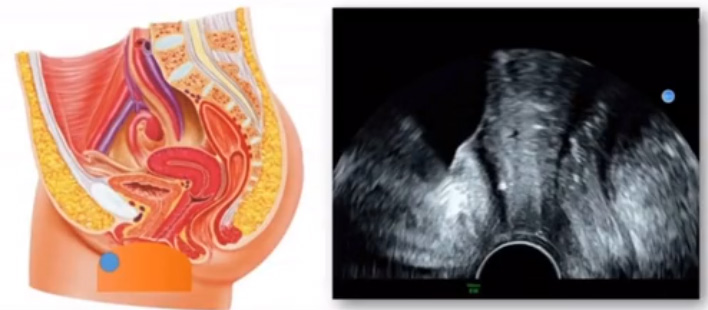

位於輸卵管的後下方,子宮兩側的後上方;借卵巢係膜與子宮闊韌帶後層相連。正常成人卵巢約4x3x2cm,跟睾丸的數值差不多,都是性器官,絕經後卵巢萎縮變小、變硬。所以絕經後婦女很難找到卵巢,主要功能:生殖和內分泌功能分泌性激素。女性的第二性征。女性內生殖器的血管分布,動脈有子宮動脈,卵巢動脈,陰道動脈,陰部內動脈。靜脈它是與動脈伴行。重要了解的是子宮動脈,子宮動脈是髂內動脈前幹的重要分支,妊娠時候血流速度會增加的,為無創性檢查胎盤血管阻力的方法。未孕期頻譜為高阻力低舒張波形;正常妊娠時血流速度增加,血流阻力下降。